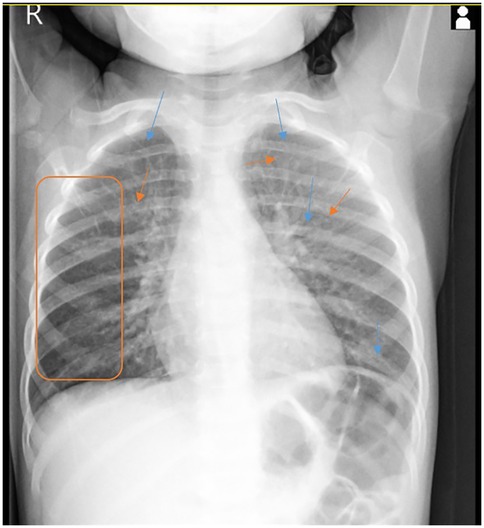

Heiner syndrome, although rare in pediatric practice, can cause cough, wheezing and only in rare cases hemoptysis. Heiner syndrome should be considered in any child presenting these respiratory symptoms and radiological evidence of alveolar infiltrates, especially when accompanied by signs of food allergy-most notably cow's milk protein allergy, although other foods seem to be involved. The use of probiotics should be evaluated with caution in these children. We report a case of a 1-year-and-6-month-old female patient who presented at the Pneumology Clinic with a one-day history of blood-tinged sputum. Although the patient had a known history of cow's milk protein allergy and well-controlled asthma, the occurrence of hemoptysis, even though in small quantities, raised concerns to the family. A second episode of hemoptysis appears when she received egg and probiotic. After correlating the patient's medical history with clinical, laboratory, and imaging findings, a diagnosis of Heiner syndrome was established. The patient received emergency treatment followed by bronchodilators, corticosteroid therapy, and restricted diet for cow's milk protein and egg. The patient's condition improved immediately after treatment and remained stable at the 5-month follow-up. The differential diagnosis with idiopathic pulmonary hemosiderosis must not be overlooked, due to its more severe clinical course and higher risk of complications.